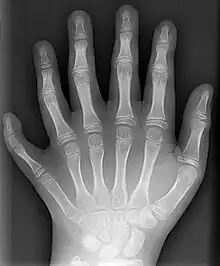

X-ray showing joints- Hand bone anatomy

The skeleton of the human hand consists of 27 bones:[10] the eight short carpal bones of the wrist are organized into a proximal row (scaphoid, lunate, triquetral and pisiform) which articulates with the bones of the forearm, and a distal row (trapezium, trapezoid, capitate and hamate), which articulates with the bases of the five metacarpal bones of the hand. The heads of the metacarpals will each in turn articulate with the bases of the proximal phalanx of the fingers and thumb. These articulations with the fingers are the metacarpophalangeal joints known as the knuckles. At the palmar aspect of the first metacarpophalangeal joints are small, almost spherical bones called the sesamoid bones. The fourteen phalanges make up the fingers and thumb, and are numbered I-V (thumb to little finger) when the hand is viewed from an anatomical position (palm up). The four fingers each consist of three phalanx bones: proximal, middle, and distal. The thumb only consists of a proximal and distal phalanx.[11] Together with the phalanges of the fingers and thumb these metacarpal bones form five rays or poly-articulated chains.

The autoimmune disease rheumatoid arthritis can affect the hand, particularly the joints of the fingers.